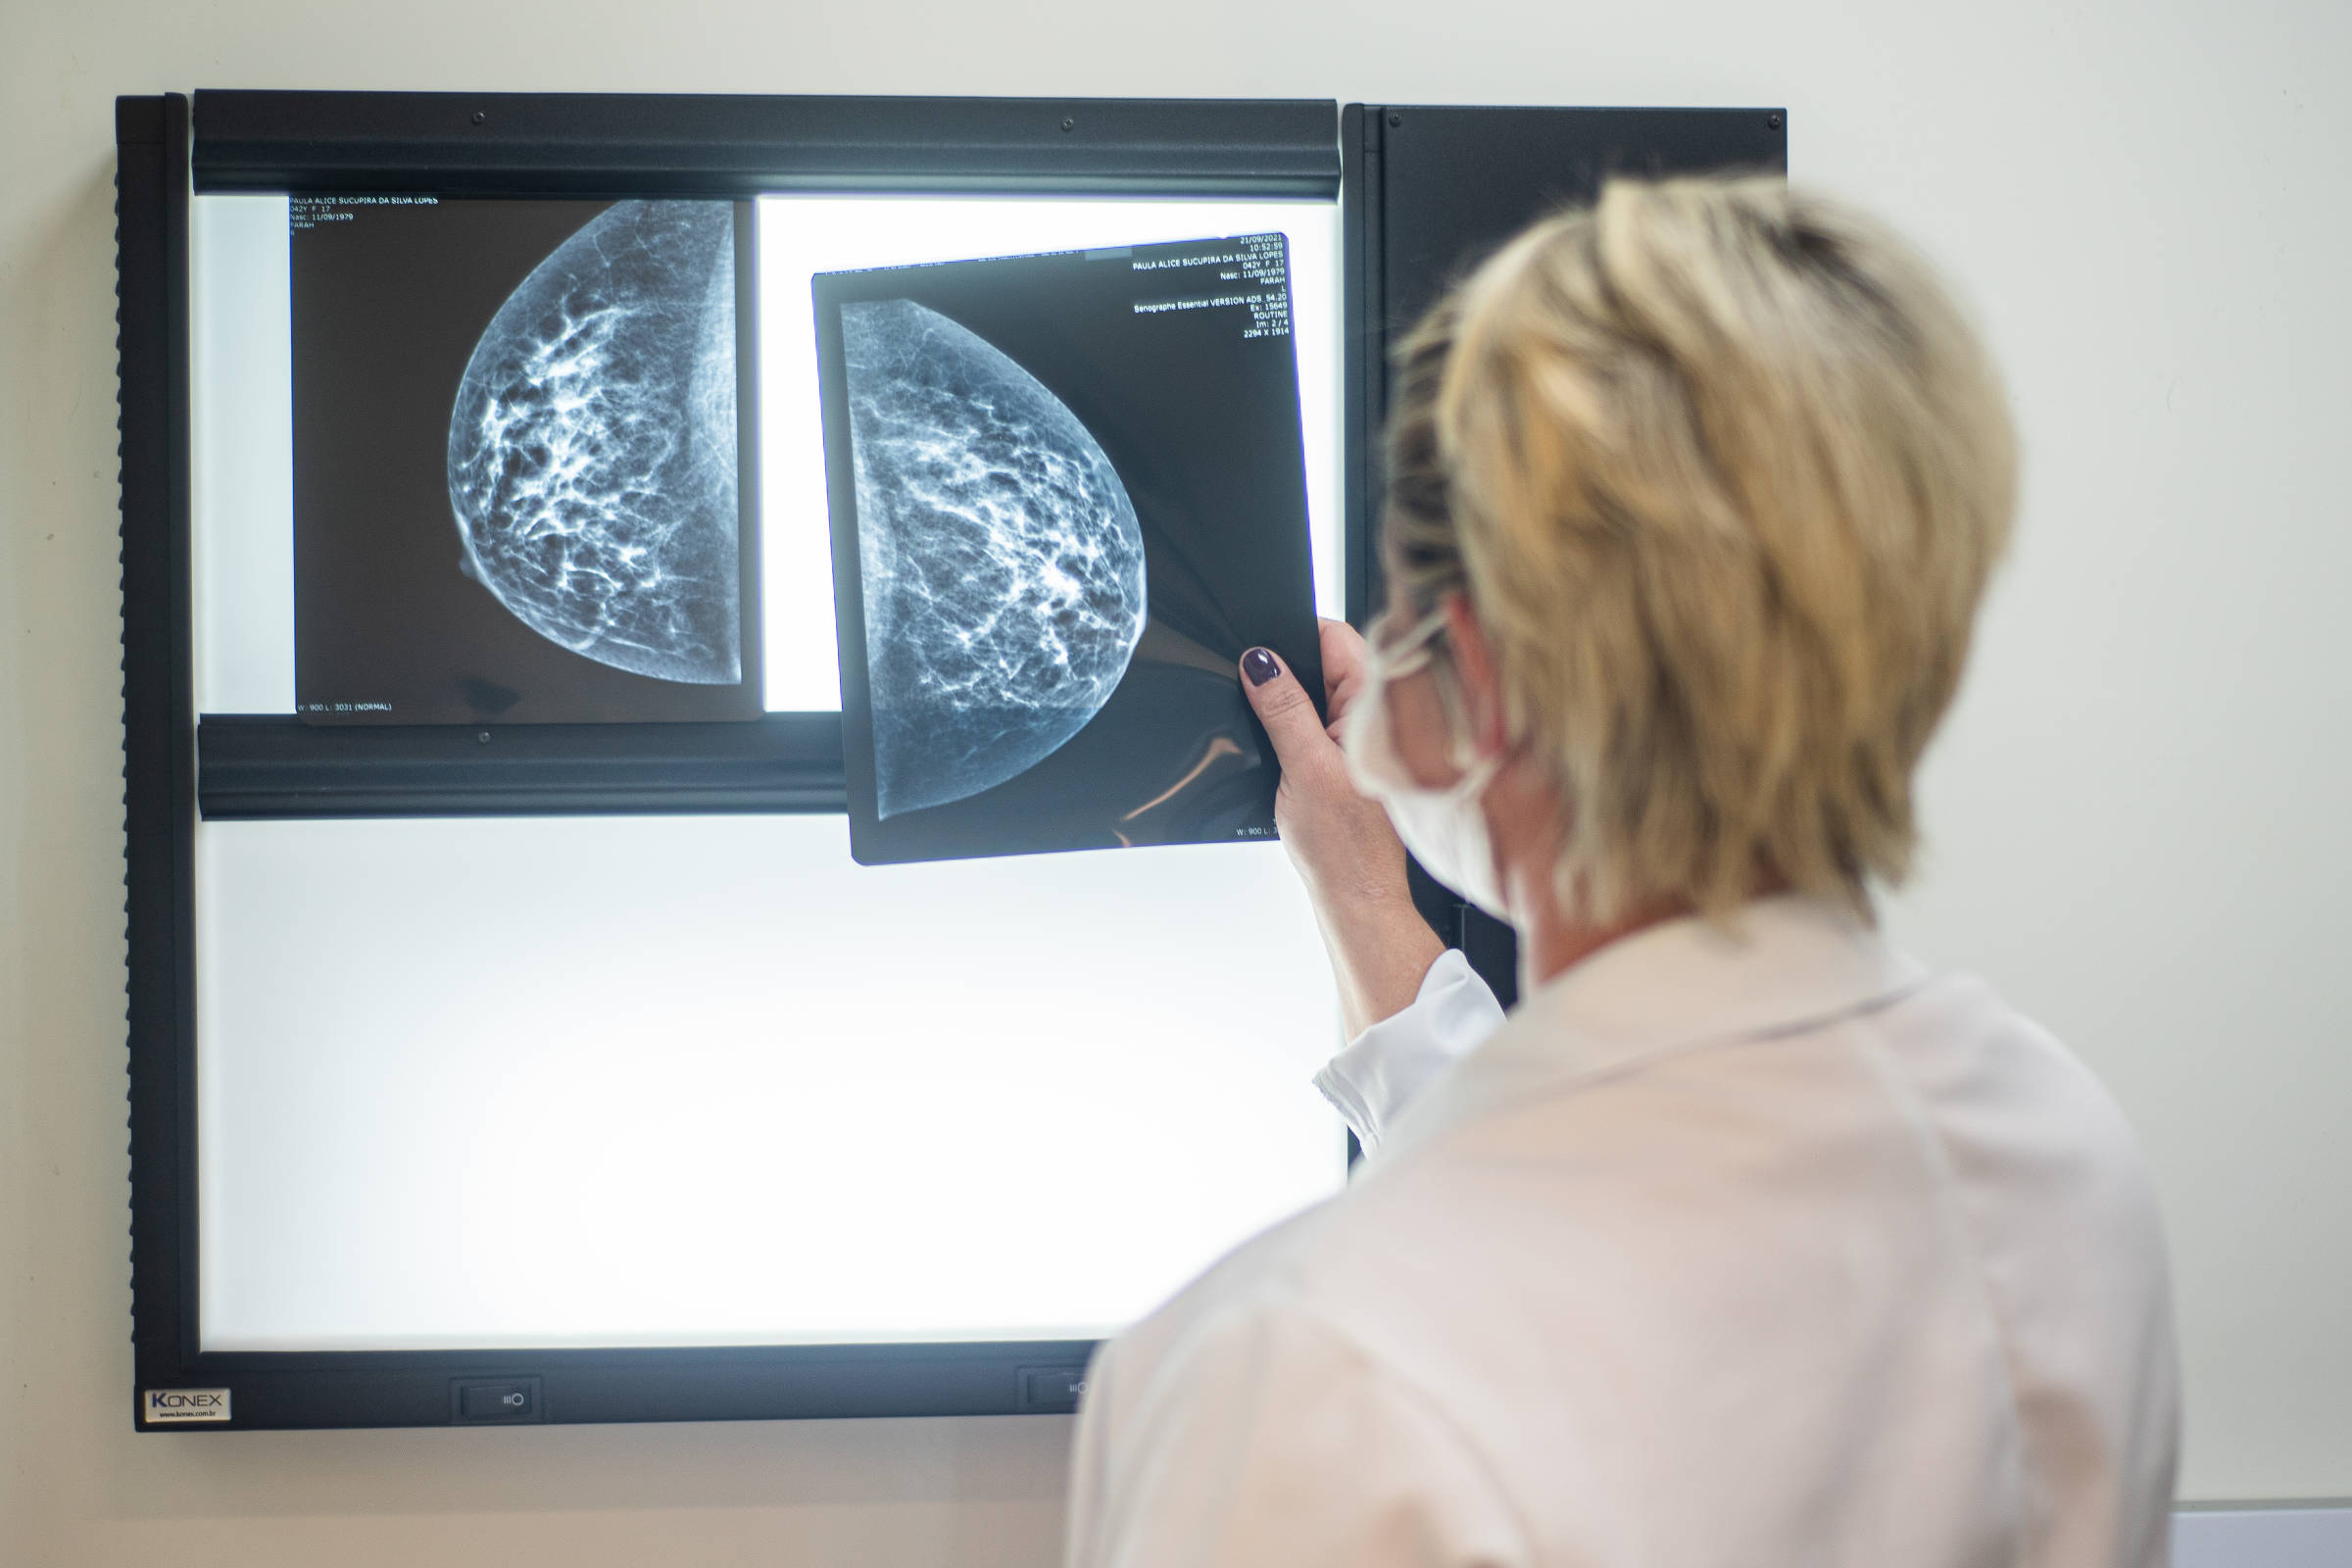

O Ministério da Saúde anunciou nesta terça-feira (23) que mulheres de 40 a 49 anos, mesmo sem sinais ou sintomas de câncer, terão o direito de realizar mamografia pelo SUS.

O ministério também anunciou a ampliação do rastreamento da doença, que inicia a partir dos 50 anos, quando a mamografia deve ser solicitada de forma preventiva a cada dois anos. A idade limite para o exame, que até então era de 69 anos, passará a 74 anos.

No caso das mulheres de 40 a 49 anos, a recomendação é que o exame seja feito sob demanda, em decisão conjunta com o médico.

“Mulheres nesta idade tinham dificuldade com o exame na rede pública de saúde por conta da avaliação de histórico familiar ou necessidade de já apresentar sintomas. Apesar disso, as mamografias no SUS em pacientes com menos de 50 anos representam 30% do total, equivalente a mais de 1 milhão em 2024”, diz a pasta.

O SUS realizou aproximadamente 4 milhões de mamografias para rastreamento e 376,7 mil exames diagnósticos no último ano.